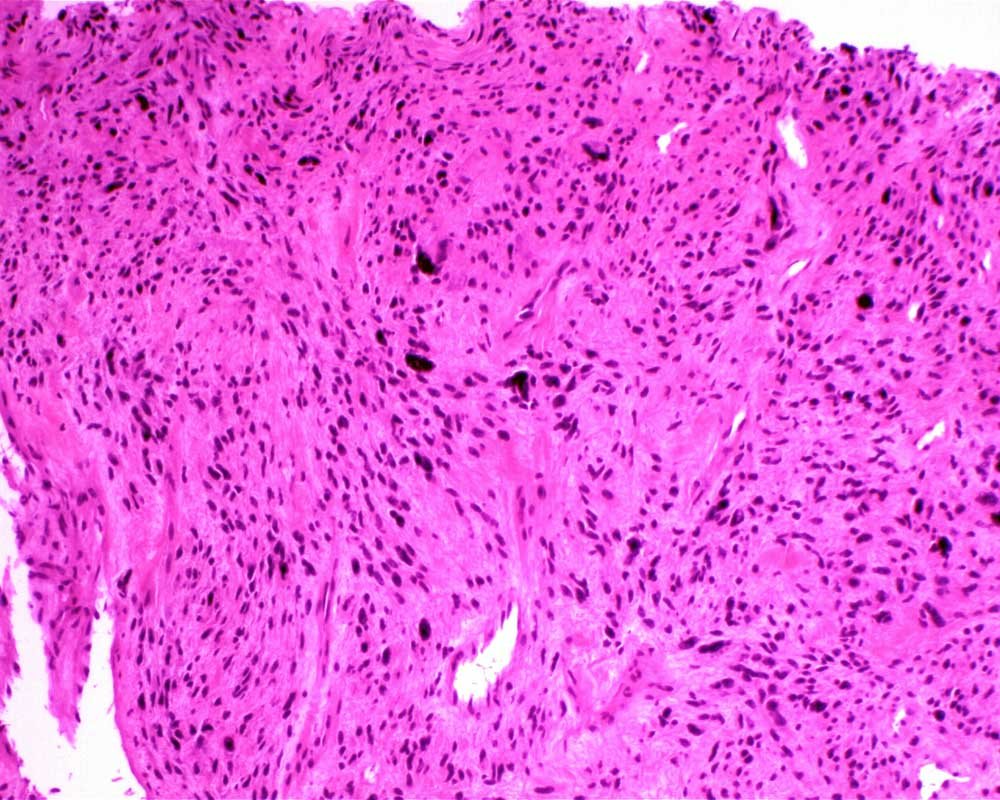

Case: ThighMass2

Final Diagnosis: